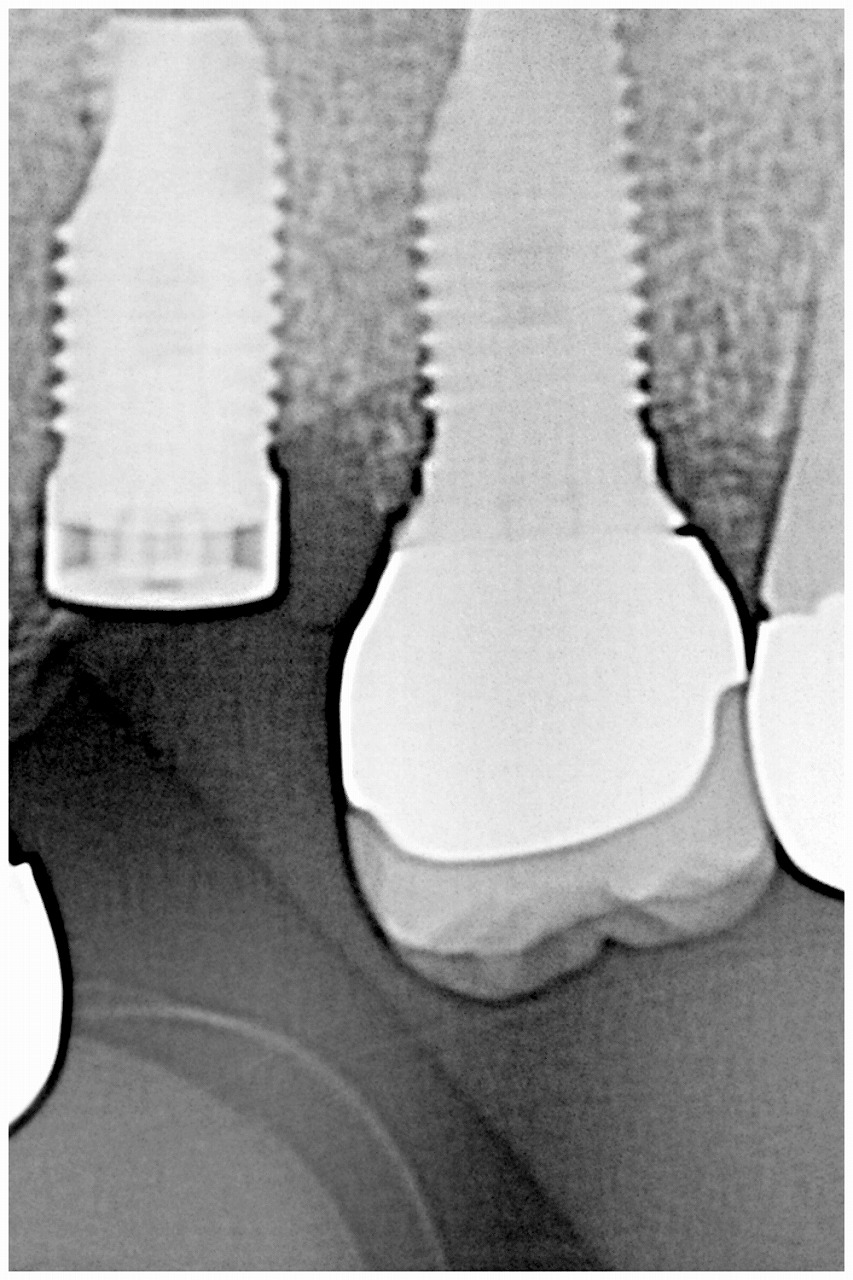

インプラント埋入時になります

隙間には骨補填材を転入しています

骨造成とソケットリフトにて上顎洞を持ち上げています

インプラント埋入から3か月待ちました